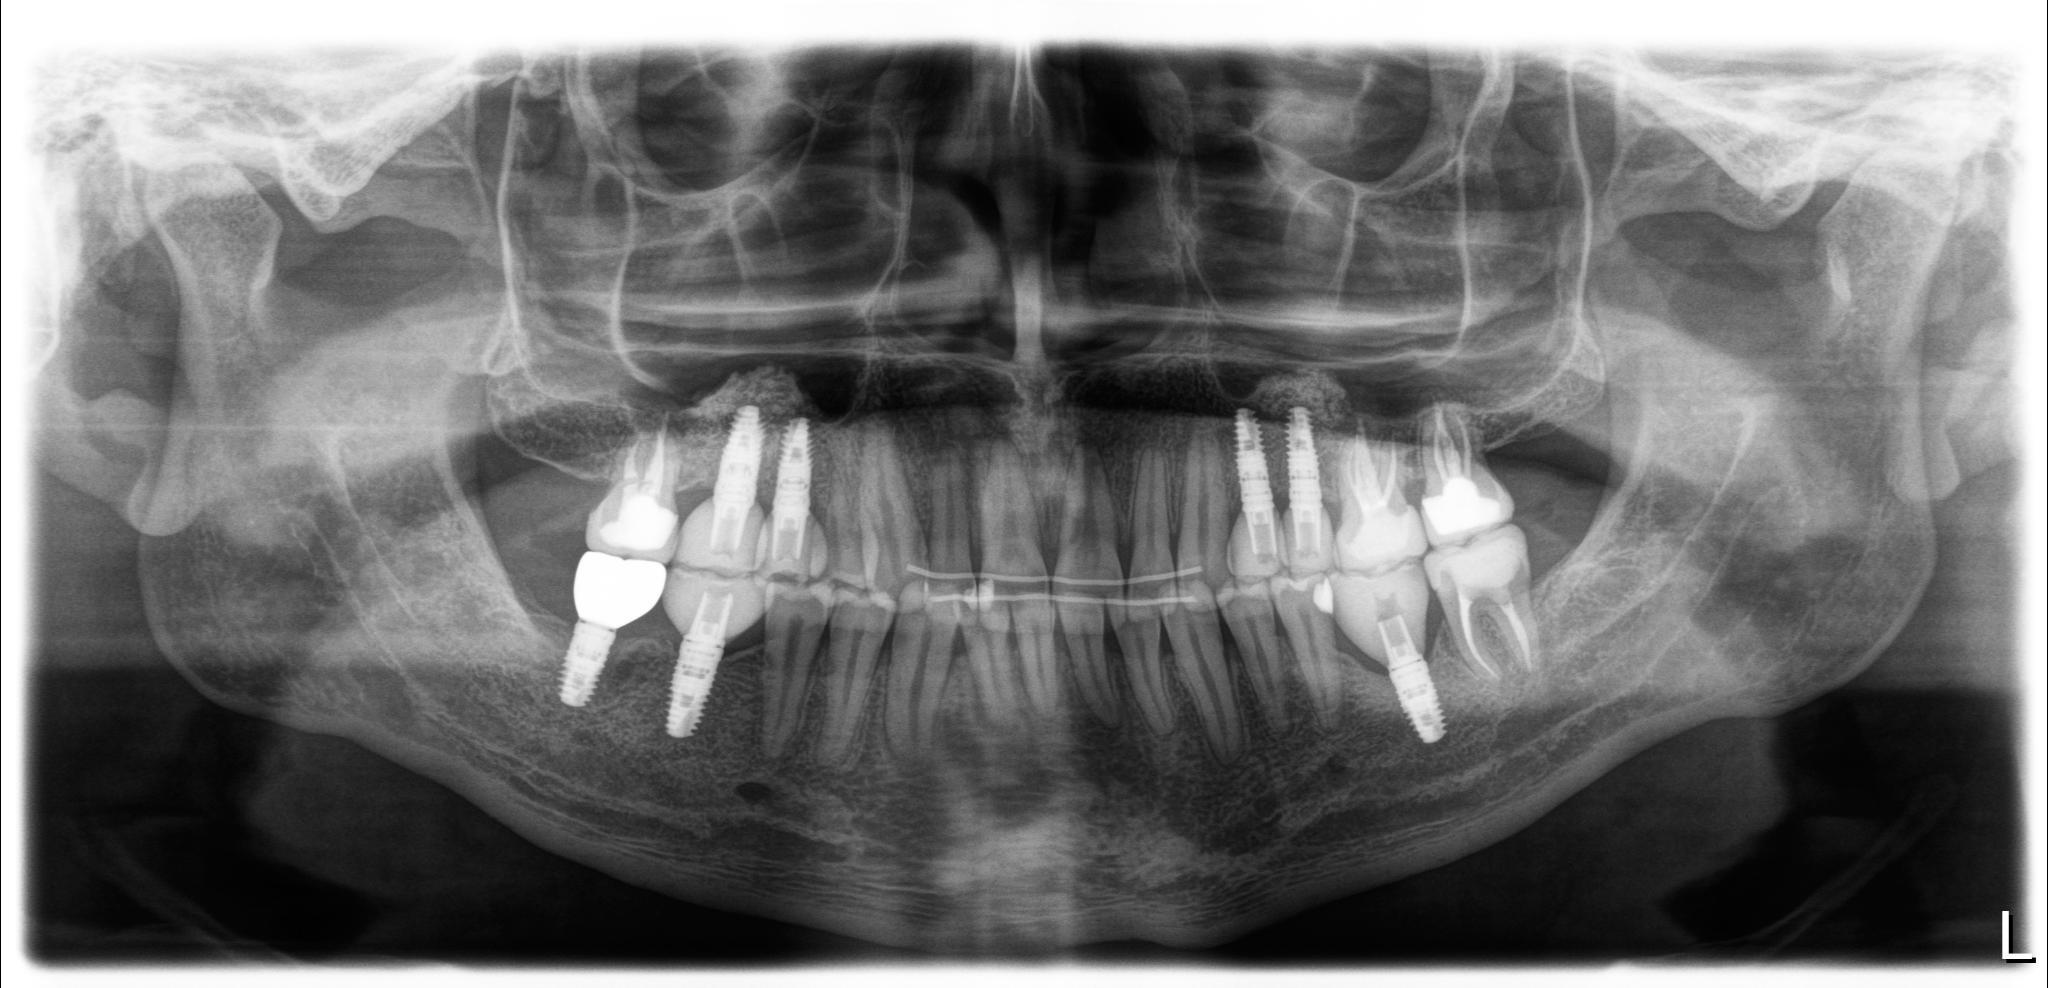

Было: